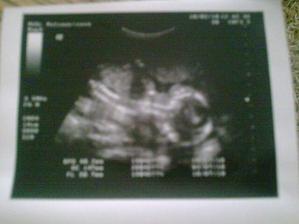

Vyrobene z velkej lasky